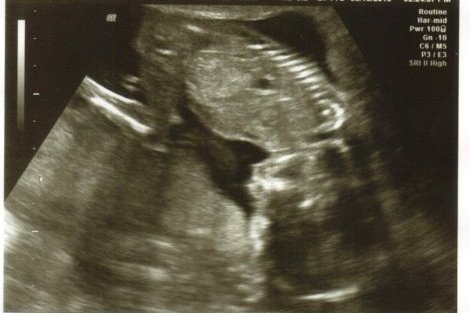

18週目になりますた。

もう写真だと姿が人間らしくなってきた^^

最近じゃー動くのが分かるようになってきたよ。

特にご飯のあとなんかは栄養をちゃんと受け取っているようで元気に動くw

性別もわかってしましました。

女だよ(・v・)

ほしかったんだおんなのこ!